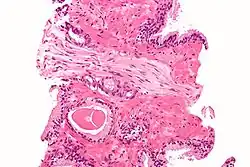

Przerzuty gruczolakoraka do płuc

Podopłucnowe przerzuty raka gruczołu krokowego szerzące się drogą naczyń limfatycznych (lymphangitic carcinomatosis)

Przekrój przez gruczoł krokowy z widocznym gruczolakorakiem stercza

W około 90–95% przypadków raka gruczołu krokowego u ludzi rozpoznaje się gruczolakoraka zrazikowego[146][147][148]. Rak rozwija się najczęściej obwodowo w części tylnej i tylno-bocznej[148]. Strefa obwodowa jest lokalizacją 68% raków, strefa przejściowa 24%, a centralna 8%[146]. Zwykle (w 85% przypadków) rak jest wieloogniskowy, a jego poszczególne ogniska mogą wykazywać różnice w obrazie histopatologicznym[148][147].